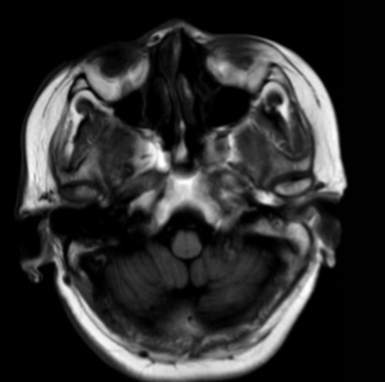

(2023-05-15 10:00,本院)行磁共振(颅脑)检查提示:右侧乳突区异常信号,考虑恶性、软骨来源肿瘤,软骨肉瘤可能性大。(集体讨论意见);脑内散在多发缺血灶。

(2023-05-12 10:15,本院)行CT(颅脑)检查提示:右侧颞骨广泛骨质破坏,伴巨大软组织肿块,性质待定,考虑肿瘤性病变,颈静脉球瘤?软骨源性肿瘤?请结合临床及病理进一步明确。